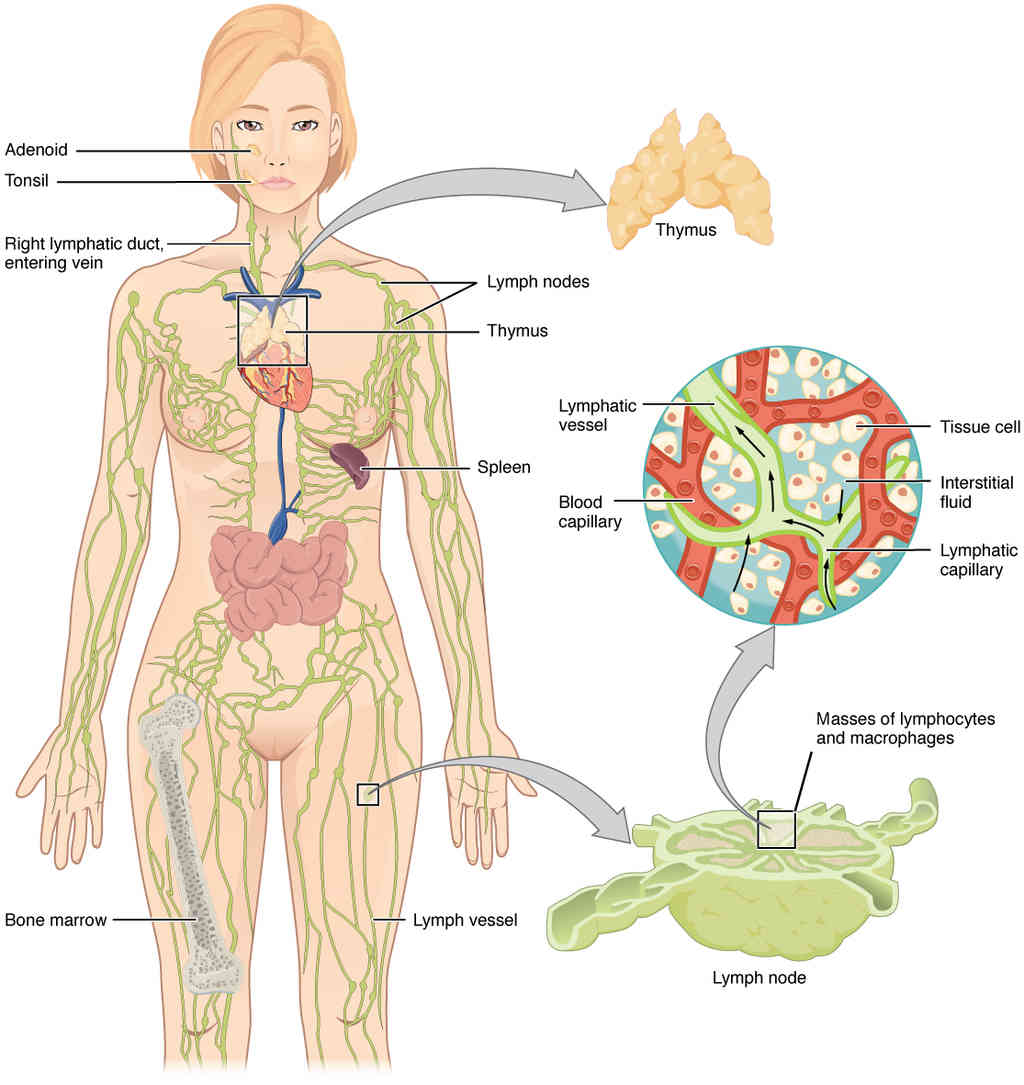

This page is under construction. For now, it is just a resource of the images found in the OpenStax Anatomy and Physiology Handbook. It wil slowly change into a revision tool. Each slide has a number. Use this to refer to the slide. When completed, it will have an unlabelled section, with labelled slides in parallel. On the unlabelled slides, write your answer and use the labelled slide to assess yourself. Keep track by also noting the number on each slide. Improvement at each attempt is important, more so than full marks on a first attempt.